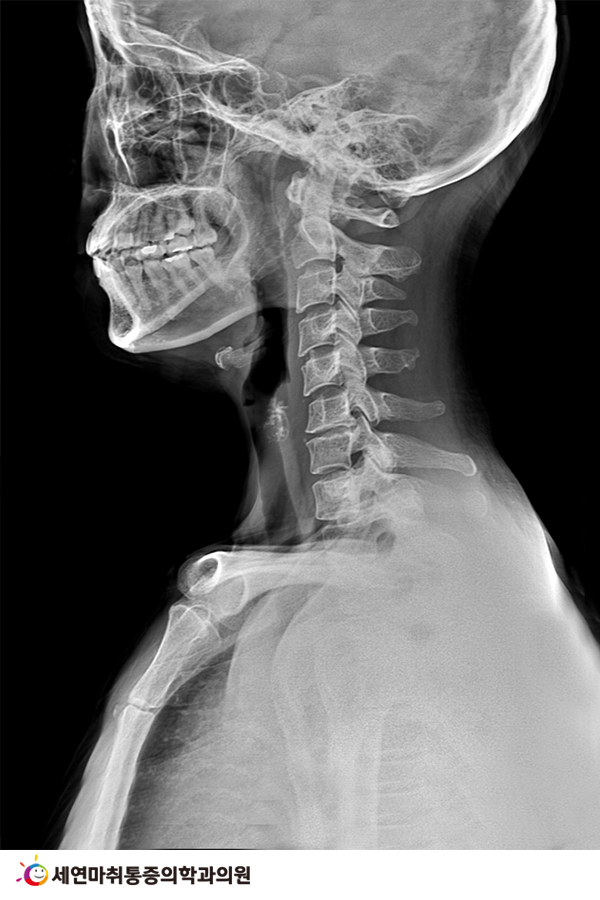

정상적인 목뼈는 C자형(머리 하중을 자연스럽게 분산시켜주고 충격을 완화)이지만 목을 앞으로 쭉 뺀 상태를 장시간 유지하게 되면 목뼈가 점점 ‘일자형’이나 ‘역 C자형’으로 변형되어 거북목증후군이 발생할 수 있습니다.

7.png

거북목증후군 환자는 정상적인 목뼈에 비해 충격을 완화하는 능력이 현저히 떨어지는데 머리의 무게가 분산되지 않은 채 그대로 목-어깨-허리까지 직접적으로 하중이 전달되어 자칫 목디스크로 발전할 수도 있으니 더욱 주의해야 합니다.